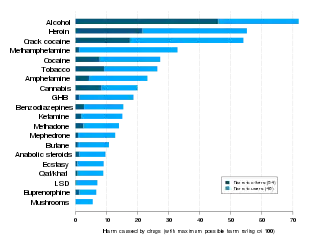

- ↑ Nutt DJ, King LA, Phillips LD (November 2010). "Drug harms in the UK: a multicriteria decision analysis". Lancet. 376 (9752): 1558–65. CiteSeerX 10.1.1.690.1283. doi:10.1016/S0140-6736(10)61462-6. PMID 21036393. S2CID 5667719.